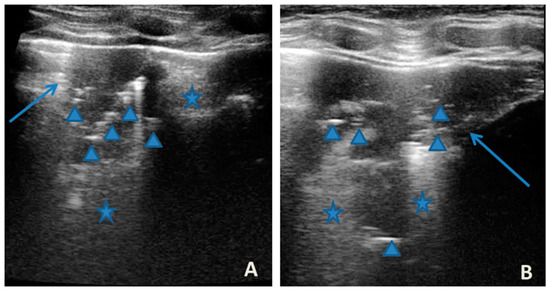

She was moderately dyspneic, in good general condition, and with stable vital signs. She had a slight rise in the indexes of inflammation. At the PED, a chest X-ray was performed to exclude an infectious picture in consideration of the auscultator finding of reduced air penetration in the right hemi thorax. The radiographic picture (Figure 4) was interpreted as an inflammatory type consolidation. Therefore, therapy for acute asthma attack and antibiotic therapy was set up, and she was hospitalized in the pediatric ward. Here, at the same time as the clinical evaluation, we performed LUS, which showed the presence of a picture of SIS, and several areas of lung atelectasis, one of which involved the middle lobe—localized in the right anterior mid-apical area (paracardiac) (Figure 5). The LUS picture was highly positive, but excluded the presence of inflammatory/infectious consolidations. On the basis of these data, the antibiotic therapy was therefore suspended, high flow oxygen therapy was set in consideration of the presence of atelectasis areas, and therapy of the moderate–severe acute attack was continued with subsequent suspension of respiratory support after about a week of therapy. Furthermore, the microbiological investigations of the airways were positive for adenovirus. An adequate preventive therapy was set up [1,2,3]. LUS follow-up showed a complete resolution of the areas of atelectasis after 2 weeks from the start of preventive therapy, and of the SIS after about 4 weeks from the start of the therapy itself.

Figure 4.

Chest radiography shows, on the right fields in the apical and basal areas, a non-specific area of reduced transparency. It also shows signs of interstitial engagement in the para-hilar position bilaterally.

Figure 5.

Grayscale lung ultrasound examination shows: an irregular pleural line in all fields explored; on the right anterior field, mainly in the medio-apical area, in the paracardiac area (A); and on the right anterior field in the basal area (B); consolidations of an atelectasis nature (arrow) poorly aerated, associated with sonographic interstitial syndrome (SIS), represented by coalescent vertical artefacts or B-lines and “white lung” areas (asterisks), which are also present in on the bilateral lateral fields (C).

In our cases (Table 1), particularly in the first three cases—children with asthma not controlled due to an inadequate preventive therapy for age, phenotype, and severity of the clinical picture [1,2]—LUS was highly positive (Figure 1, Figure 3 and Figure 5). It showed the presence of lung atelectasis, which resolved slowly after weeks of therapy of the acute attack and the beginning of adequate preventive therapy. On the contrary, in case 4 and 5—children with asthma well controlled by adequate preventive therapy—LUS was not highly positive (Figure 6 and Figure 7). In fact, it did not show large atelectasis, but a slight SIS in case 4, and a SIS suggestive of viral infection of the small airways in case 5 [14,15].